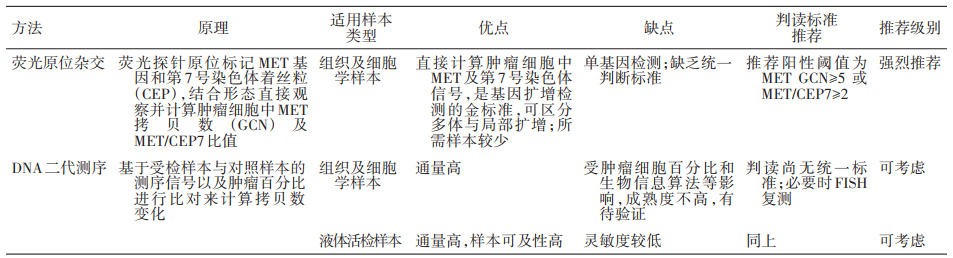

重磅!首部《非小细胞肺癌MET临床检测中国专家共识》正式发布!...

重磅!首部《非小细胞肺癌MET临床检测中国专家共识》正式发布!...